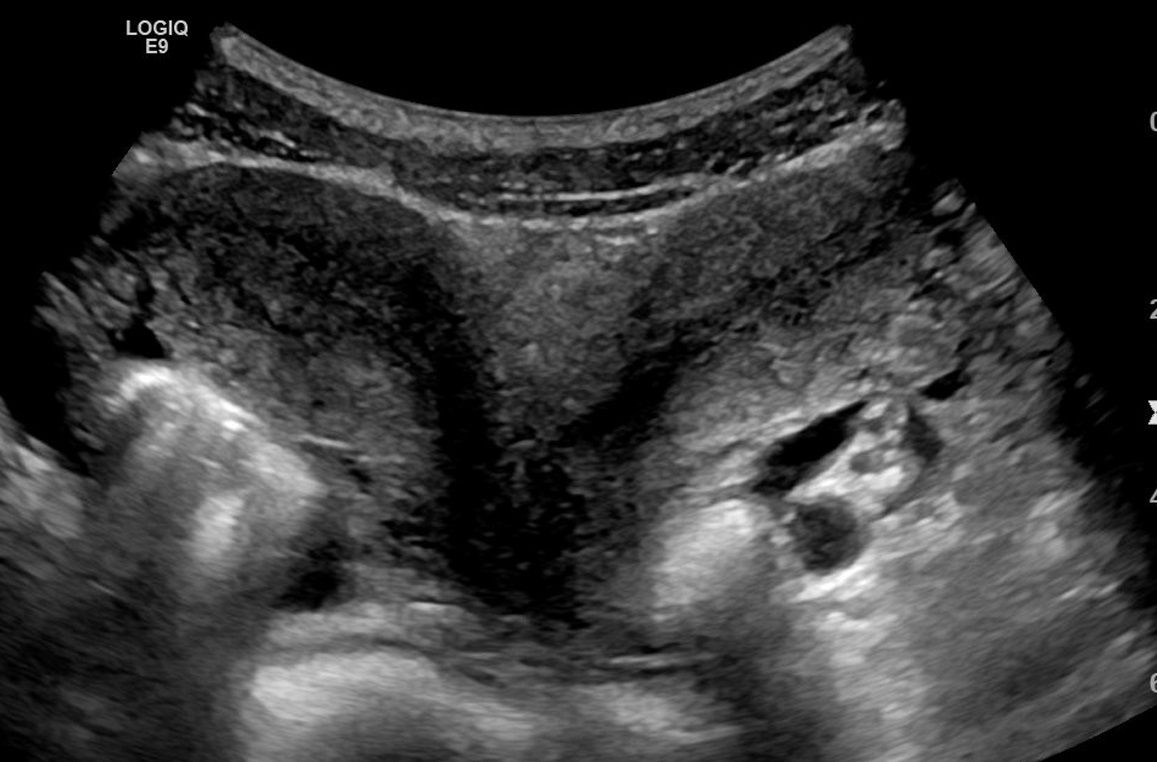

Statt der normalen Birnenform zeigt der Uterus didelphys eine V-Form.